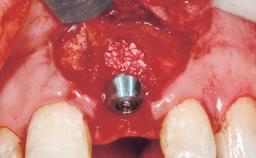

A 39-year-old male patient presented with a chief complaint of discomfort and gingival discoloration around his maxillary left central incisor. He was in good general health and was a non-smoker. His past dental history was significant because of the traumatic fracture of tooth 21 in a sporting accident at age 13. Initial dental treatment included endodontic therapy and a full-coverage restoration. The patient became symptomatic 5 years later, when structural failure of the tooth resulted in the dislodgment of the crown. Endodontic retreatment, apical surgery, and post-and-core restoration were performed.

Bone Augmentation Horizontal|Staged

Augmentation Materials Xenogenous|Membrane

Bone Volume Deficient horizontally, requiring prior grafting